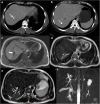

Objectives: We aim to illustrate the multimodal imaging spectrum of hepatic involvement in tuberculosis (TB). Whilst disseminated tuberculosis on imaging typically manifests as multiple small nodular lesions scattered in the liver parenchyma, isolated hepatic tuberculosis remains a rare and intriguing entity.

Methods: Indubitably, imaging is the mainstay for detection of tubercular hepatic lesions which display a broad spectrum of imaging manifestations on different modalities. While sonography and computed tomography (CT) findings have been described in some detail, there is a paucity of literature on magnetic resonance imaging (MRI) features. Due to a significant overlap with other commoner and similar appearing hepatic lesions, hepatic tuberculosis is often either misdiagnosed or labelled as indeterminate lesions. This article is a compendium of cases highlighting the spectrum of imaging patterns that can be encountered in patients with isolated primary hepatic tuberculosis as well as disseminated (secondary) disease. Rare patterns of primary disease such as tubercular cholangitis, hypervascular liver masses, and those with vascular complications are also illustrated and discussed.

Teaching points: • Hepatic TB has myriad imaging manifestations and is often confounded with neoplastic lesions. • Imaging patterns include miliary TB, macronodular TB, serohepatic TB and tubercular cholangitis. • Concurrent splenic, nodal or pulmonary involvements are helpful pointers towards the diagnosis. • Miliary calcifications along the bile ducts are characteristic of tubercular cholangitis. • Histological/microbiological confirmation is often necessary to confirm the diagnosis.